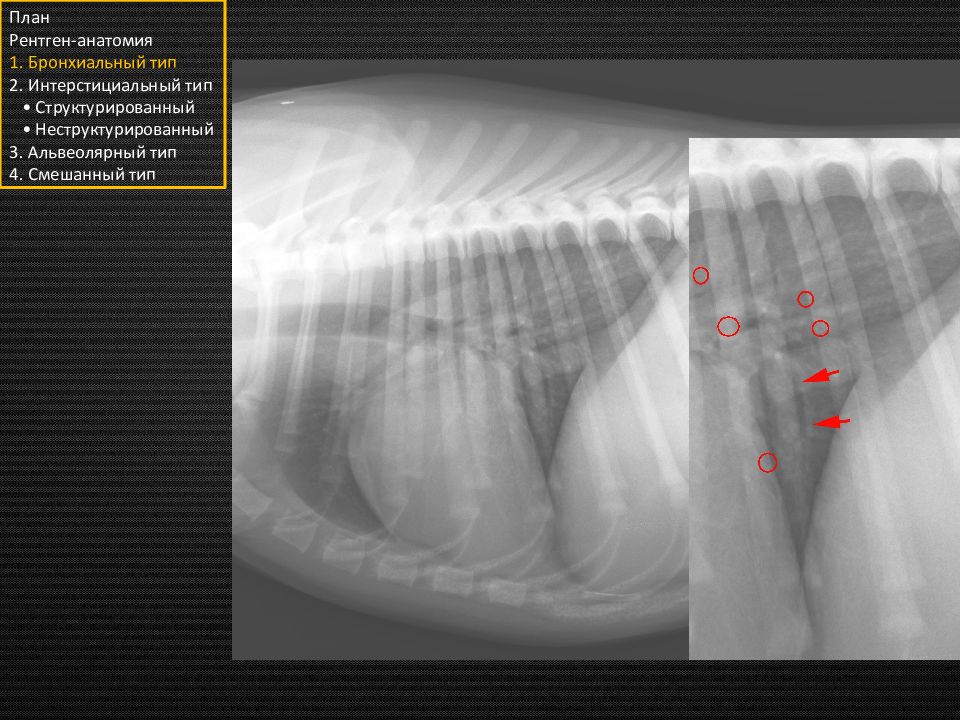

Слайд 28

План Рентген-анатомия 1. Бронхиальный тип 2. Интерстициальный тип • Структурированный • Неструктурированный 3. Альвеолярный тип 4. Смешанный тип Сосуды!